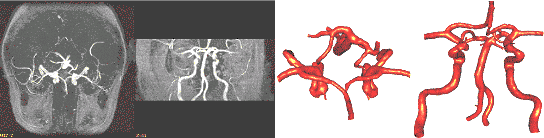

3.3. Circle of Willis

The region growing segmentation approach was applied to

the construction of realistic anatomical models of the circle

of Willis from 3D MRA images. The MIPs of the anatomical

images before and after applying the region growing procedure

are shown in Fig. 5a and 5b, respectively. The reconstructed

model after smoothing and optimization is shown in Fig.

5c.

a)

b) c)

Figure 5. Reconstruction

of the circle of Willis from MRA images: a) MIP of original

images; b) MIP after region growing; c) reconstructed surface

model.

a) b)

Figure 6. Finite element

grid of the circle of Willis: a) final geometrical model

after cutting arterial branches;

b) surface of the final finite element grid with uniform

element size distribution.

The final geometrical model after cutting several arterial

branches along contours of geodesic distances is shown in

Fig. 6a. This model was then used to generate a finite element

grid with uniform element size distribution. The final mesh

(Fig. 6b) contained approximately 4 million elements.